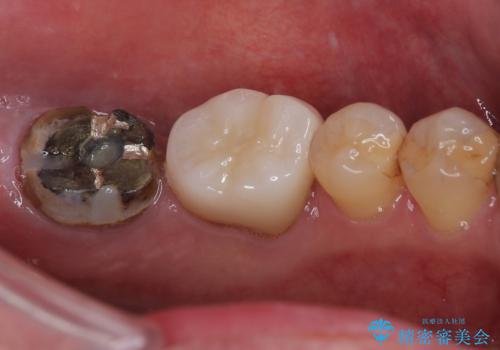

- 左下の奥歯の被せものが外れ、噛むと痛みがあると来院された患者様です。

歯根破折の疑いがあり、顕微鏡下で染色して確認したところ破折線は認められませんでした。

そのため再根管治療の適応と判断し、治療を進めていくこととしました。